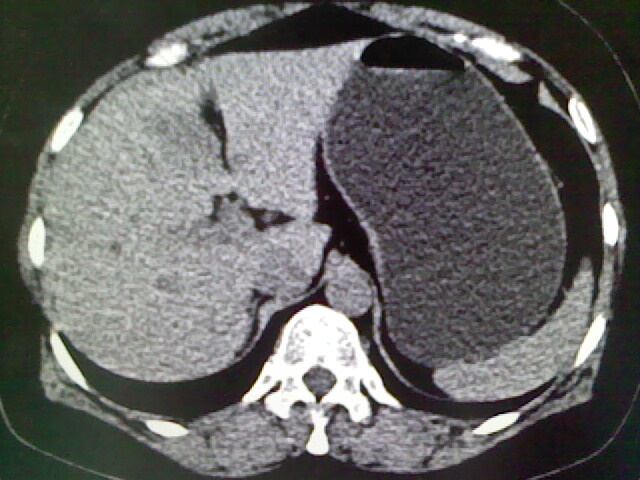

以下是引用卜一在2009-4-2 13:26:00的发言:[br]胆囊颈部结石伴胆囊炎!另:建议增强,待除外肝内占位及胆囊占位!

以下是引用liaoqiang在2009-4-2 16:23:00的发言:[br]胆囊是否切除?胆囊颈区致密影考虑金属夹?结石?肝脏右叶低密度影,考虑增强。